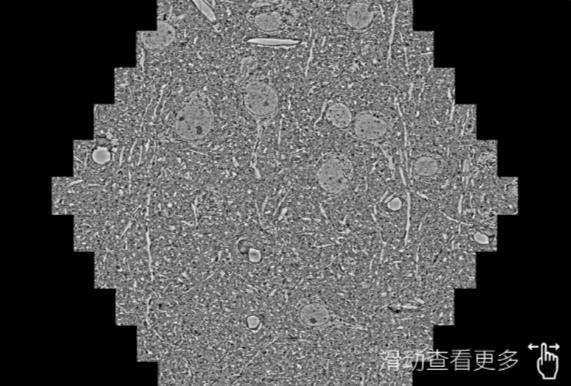

鼠脑切片。左图使用丽水蔡司丽水扫描电镜MultiSEM706对165μmx143pm面积区域成像,耗时仅需1.5秒。右图为鼠脑切片中30μm区域放大效果。样品由芝加哥大学B.Kasthuri提供。